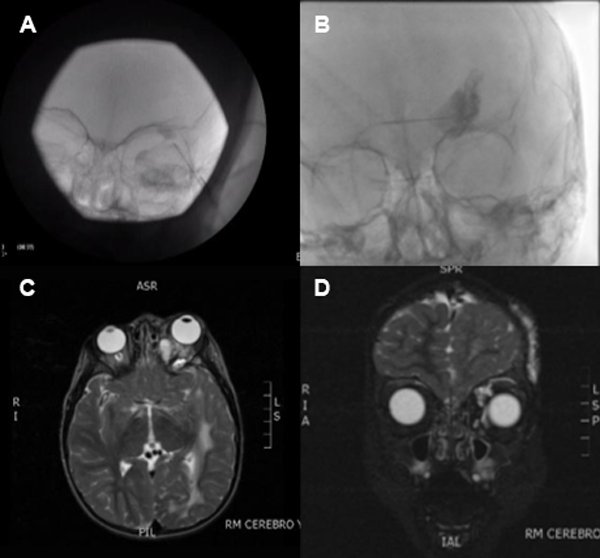

Se examinaron en el servicio 14 pacientes con patología vascular de compromiso orbitario y/o palpebral (tabla 1). De ellos, tres fueron hemangiomas infantiles (HI) (fig. 1), todos de sexo femenino tratados con betabloqueantes; seis malformaciones linfáticas con marcado predominio de sexo femenino, la mayoría tratados con escleroterapia guiada por control radiológico, al igual que los cuatro casos de malformación venolinfática, y un caso de fístula carótido-cavernosa de alto flujo, tratada con embolización. Necesitaron retratamiento por recidiva 3 malformaciones venolinfáticas y 1 linfática pura. El rango etario de aparición de signos clínicos fue desde el nacimiento hasta los 12 años, con una media de 3,6 años y una mediana de 1,67 años, pero característicamente los HI se manifestaron en una edad promedio de 1 mes de vida, mientras que en las malformaciones vasculares fue de 4,5 años. El signo oftalmológico más manifiesto fue la proptosis (8 casos), seguido por el estrabismo (6 casos). La localización más común fue órbita con asociación a párpado inferior. Hubo 5 casos con hallazgos vasculares asociados extra-orbitarios/palpebrales. La amplia mayoría de casos obtuvo una resolución clínica de su cuadro de base (93%). Dentro de los métodos de imágenes más utilizados se encontró en primer lugar la ecografía (78%), seguido por la resonancia magnética (64%). En las figuras 2 y 3 se presentan dos casos y los estudios descriptos y la escleroterapia guiada bajo control radiológico.

Figura 1. Hemangioma en párpado superior postratamiento de 2 meses con timolol 0,5% con reducción de lesión de canto interno y desaparición de la que se hallaba en tercio medio contigua.

Figura 2. A y B) Escleroterapia con control radiológico realizado. C y D) Resonancia magnética control (corte sagital y coronal respectivamente) de paciente con malformación venolinfática en órbita, párpado superior y región supraciliar. Recibió tratamiento con escleroterapia y retratamiento a los 4 años, asociado a fístula arteriovenosa dural tratada, cavernoma supratentorial, malformación venolinfática microquística en paladar y mejilla izquierda.